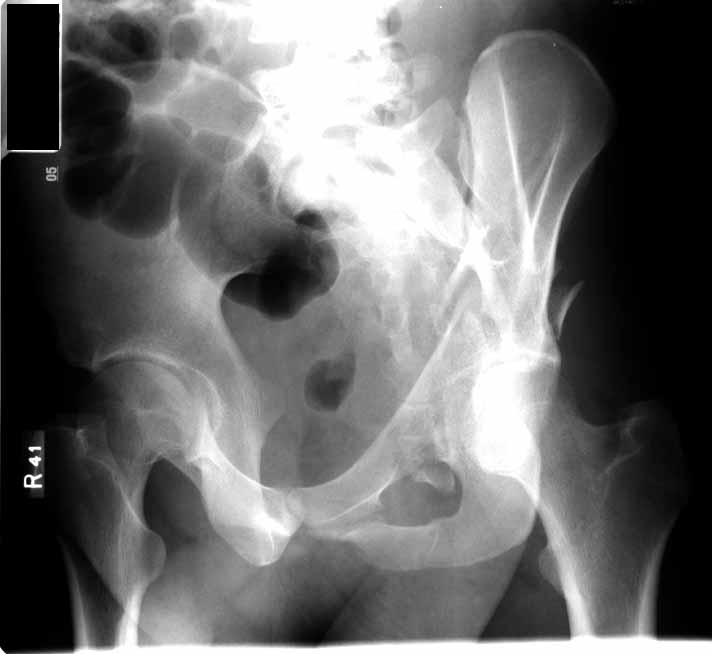

Subject: Acetabular Fx - both columns

This is an 18 yo male involved in an MVA 2 days ago. Isolated injury other than some rib fxs. I had trouble interpreting the xrays, but the CT shows a both column fracture with secondary congruence (I think). The plain films show significant gapping of the anterior column, but the CT shows fairly little at the dome.

Reducing the anterior column should be straightforward through the ilioinguinal approach, but will the piece of the posterior column articular surface go with it, and if it doesn't will this be reducible after reducing the anterior component? Or is this true secondary congruence and what are the consequences of letting it heal as is?

Yes, the posterior column dominant fracture fragment will follow the anterior column. Some surgeons would concentrate on the articular reduction and tolerate the slight residual medial displacement of the hip from the intact ilium. Both can be improved.

You'll notice by CT that there is an intact labral "hinge" which usually indicates that these 2 dominant articular fragments will behave together intraop. But you'll still need to expose, clean, and clamp them before fixation. And your operative goal is to have the articular reduction be perfect on the postop CT...can you make this one better?

You'll notice that the anterior column is incomplete peripherally...this lends stability if you elect to treat him without surgery, and indicates an osteotomy at the iliac crest to complete the fracture and allow its mobilization for cleaning and reduction, should you choose surgery.